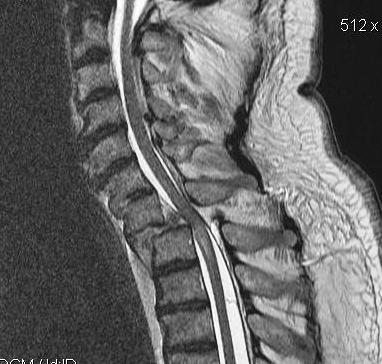

MRI

Cervico-medullary angle < 135 degrees

- the line parallel to ventral side of medulla oblongata

- the line parallel to the ventral side of the upper cervical cord

- normal angle is 135-175°

- <135° consistent with vertical settling and correlated with myelopathy

From: Guo et al Sci Rep 2019. http://creativecommons.org/licenses/by/4.0/.